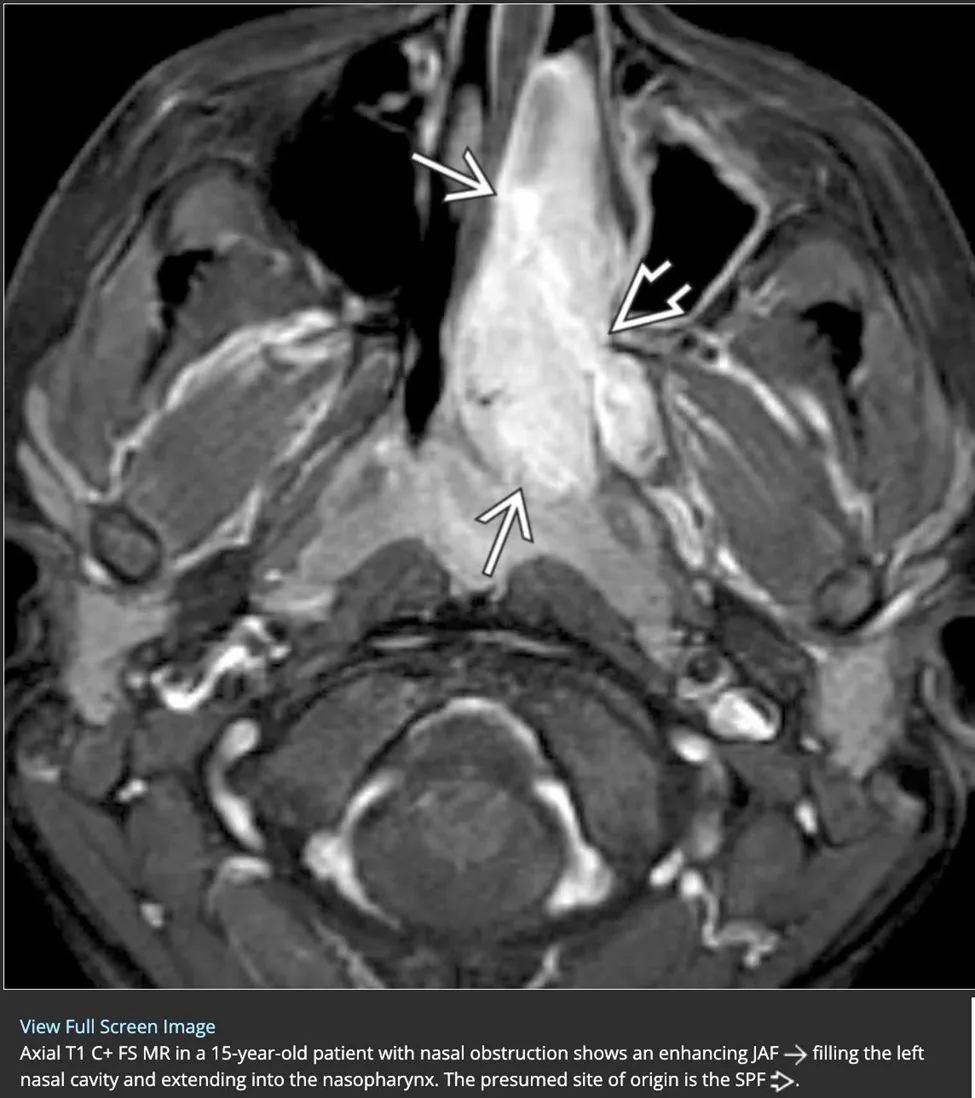

Juvenile nasopharyngeal angiofibroma commonly spreads from the sphenopalatine foramen into the {{c1::nasopharynx}} and {{c2::pterygopalatine fossa}} with associated bony remodeling

<b>Juvenile nasopharyngeal angiofibroma commonly </b>spreads from the sphenopalatine foramen into the {{c1::<u>nasopharynx</u>}} and {{c2::<u>pterygopalatine fossa</u>}} with associated bony remodeling